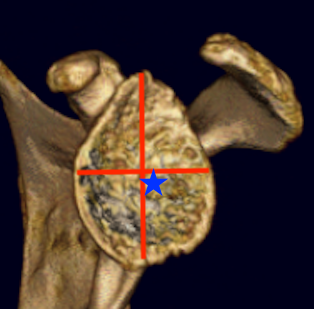

Glenoid morphology, bone stock and version

Issues

1. What is the morphology?

2. Is there sufficient bone stock for glenoid replacement?

3. Does version need to be addressed?

Walch classification glenoid morphology

Type A - centred humeral head, concentric wear, no humeral head subluxation

A1: minor central erosion

A2: major central erosion with humeral head protrusion

Type B - posterior subluxation of the humeral head, with biconcave glenoid and asymmetric wear

B1: narrowing of the posterior joint space

B2: biconcave glenoid with posterior rim erosion and retroverted glenoid

B3: monoconcave glenoid with > 15° retroversion or >70% posterior humeral head subluxation or both

Type C

C1: dysplastic glenoid with >25° retroversion

C2: biconcave, posterior bone loss, posterior translation of the humeral head

Type D: glenoid anteversion or anterior humeral head subluxation <40°

Type A2 Type B1

Type B2 Type B3

Type B3